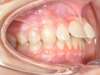

Cas 4 : Description

Chevauchement sévère. Traitement multibague sans extraction.

Avant

Après